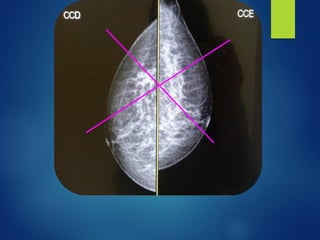

CRITÉRIOS DE AVALIAÇÃO

▪ Nessa incidência devemos

▪ A não visualização da área

▪ Deve-se incluir

▪ Mamilo deve estar em perfil

▪ Ausência de dobras

▪ Radiografias

▪ O músculo

▪ Se o músculo peitoral não estiver presente na

▪ O valor da distância mamilo - porção posterior da

▪ Obtém-se o valor medindo a distância do mamilo até o